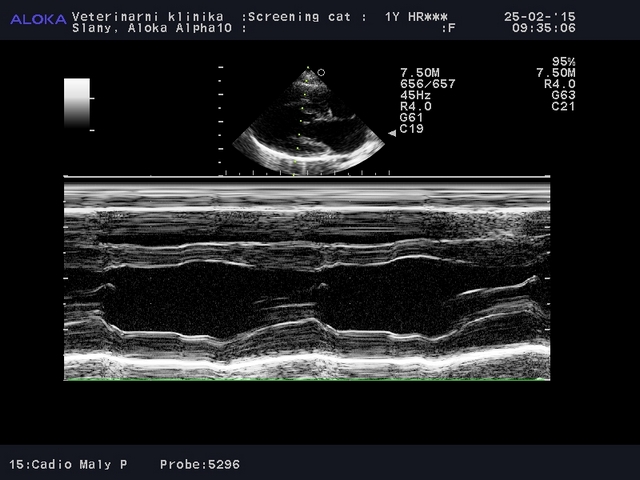

Vyšetření koček musí být prováděno pouze pomocí kvalitního ultrazvuku a kardiologické sondy, která zhotoví snímky v odpovídající kvalitě. Všechny snímky z vyšetření musejí být uloženy.

IVSd (interventricular septum diameter in diastole) - šířka mezikomorové přepážky při diastole (fáze roztažení)

LVDd (left ventricular diameter in diastole) - šířka levé komory při diastole

PWd nebo LVWd (posterior wall diameter in diastole, left venticular wall in diastole) - šířka stěny levé komory při diastole

IVSs (interventricular septum diameter in systole) - šířka mezikomorové přepážky při systole (fáze smrštění)

LVDs (left ventricular diameter in systole) - šířka levé komory při systole

PWs nebo LVWs (left ventricular diameter in systole) - šířka stěny levé komory při systole

EF (ejection fraction) - znamená více méně kolik krve je vytlačeno z levé komory v době smrštění (systoly)

FS (fractional shortening) - tzv. stažitelnost srdce, zjednodušeně znamená více měně sílu smrštění srdce

Ao (Aorta) - šířka aorty, tj. hlavní tepny

LA (left atrium) - šířka levé předsíně

LA/Ao - podíl levé předsíně k aortě (maximálně se připouští kolem 1,5 - 1,6), počítá se ze dvakrát měřených hodnot